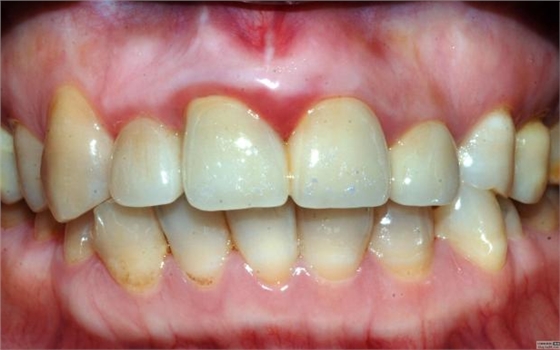

最近接到這樣一位患者,上前牙氧化鋯聯(lián)冠修復(fù)不足一年時間,現(xiàn)患者主訴左上前牙疼痛來診,檢查發(fā)現(xiàn)上前牙冷熱無反應(yīng),扣診(++),牙齦紅腫,探出血,冠邊緣不密合, X片示基牙全部已做根管治療,但是根管充填全部欠填。

先不評論修復(fù)體的顏色、形態(tài)、密合性及生物學(xué)寬度的問題,就患者而言對修復(fù)體還是比較滿意的,是因為修復(fù)后不久牙齒開始疼痛,吃了好多藥也不起作用才來就診檢查的,但患者剛開始不愿拆冠,經(jīng)過詳細(xì)的溝通后才同意拆冠——冠延長術(shù)——根管再治療——愈合——重新修復(fù)??梢娀颊唠m然花了較高的費用,但對我們醫(yī)生的要求還是很低的,但就是這么低的要求也不見得所有醫(yī)生能夠滿足患者。這個患者即使冠沒有問題,也得拆冠?;颊咭彩茄捞鄄艁碓\治的,在修復(fù)之前一定要做完善的根管治療。